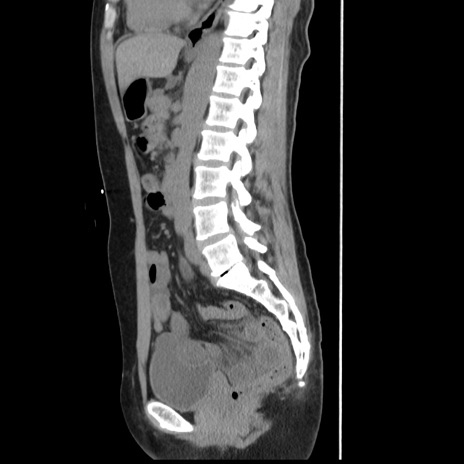

症例10(矢状断像)

【症例】 50歳代女性

【主訴】 腹痛

【現病歴】前日生レバーを食べた。今朝に排便あり。 昼前に突然発症の腹痛を生じ、当院救急外来を受診した。

【既往歴】 子宮筋腫にてで子宮全摘後

【身体所見】 意識清明、腹部:平坦、軟、下腹部やや左を中心に圧痛・反跳痛あり、筋性防御あり

【データ】WBC 7800、CRP 0.07